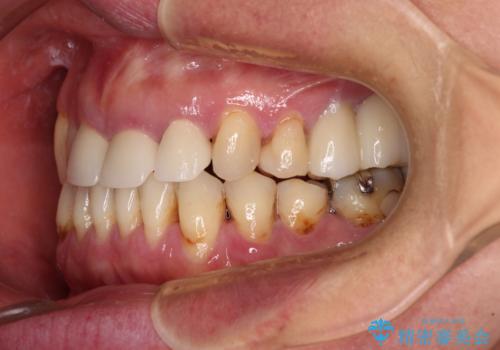

反対咬合や欠損を治療したい インビザライン矯正とオールセラミックブリッジ

- 虫歯治療がうまく進まないとのことで来院された患者様です。

虫歯治療や欠損補綴治療も必要でしたが、前歯が反対咬合であったので、セラミッククラウンやブリッジによる治療と並行して矯正治療を提案しました。

仕事柄海外出張が多いとのことで、虫歯治療後にインビザラインにて矯正治療を行うこととしました。